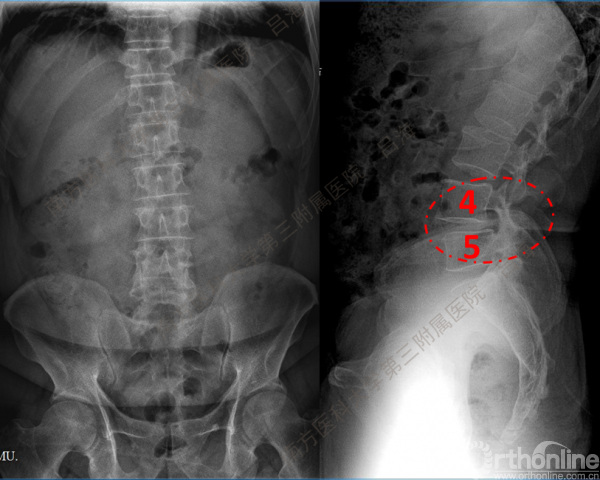

随着社会老龄化进程加快,胸腰椎退行性病变的治疗已经成为脊柱学术界的一个热点话题。MIS-TLIF手术可以治疗多种不同的胸腰椎退行性疾病,南方医科大学第三附属医院吕海教授结合病例为我们一一展示了该术式在治疗不同胸腰椎疾病时的具体手术过程。